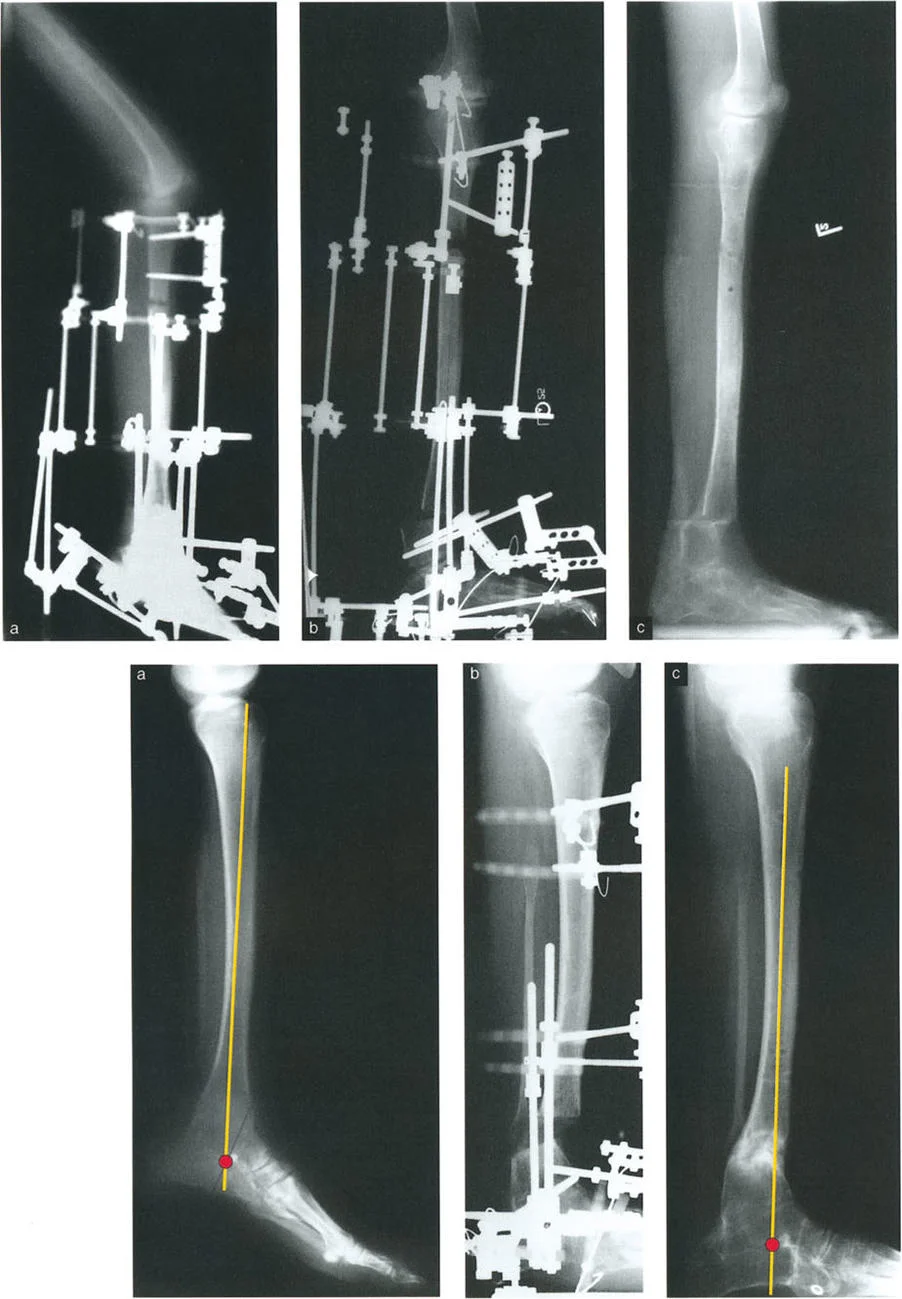

* الأشعة السينية (X-rays) الواقفة لكامل الطرف السفلي: هذه الأشعة ضرورية لتقييم المحاذاة الكلية للطرف السفلي تحت تأثير وزن الجسم. يطلب الأستاذ الدكتور محمد هطيف صورًا شعاعية كاملة الطول للساق أثناء الوقوف (Full-length standing alignment films) لتقييم المحور الميكانيكي للساق وتحديد زوايا المفاصل بدقة.

* الأشعة السينية الجانبية والامامية الخلفية للكاحل: تُظهر هذه الصور تفاصيل مفصل الكاحل نفسه، بما في ذلك زاوية القصبة الأمامية البعيدة (ADTA) وزاوية القصبة الوحشية البعيدة (LDTA)، وهي زوايا حاسمة لتحديد التشوه في المستويين الأمامي والسهمي.

* منظر سولتزمان (Saltzman View): هذا المنظر الإشعاعي الخاص يتم الحصول عليه بزاوية 20 درجة لقياس محاذاة عظم العقب (Calcaneus) بالنسبة لقصبة الساق، وهو أمر بالغ الأهمية لتقييم تعويضات القدم الخلفية.

* رسم المحاور الميكانيكية والتشريحية: لتحديد نقطة مركز دوران التشوه (CORA)، وهي النقطة التي يجب أن تتم عندها الجراحة لتصحيح التشوه بأقل قدر من المضاعفات.

* فهم آليات التعويض: تحليل كيف تحاول القدم والكاحل تعويض التشوه في الساق، وما هي حدود هذا التعويض.

* التخطيط الجراحي الدقيق: استخدام هذه البيانات لوضع خطة جراحية مفصلة للغاية، بما في ذلك نوع قطع العظم، وموقعه، وكيفية تحقيق التصحيح المطلوب.

تُعد مبادئ الدكتور درور بالي حجر الزاوية في جراحة تصحيح تشوهات العظام. تركز هذه المبادئ على تحديد "مركز دوران التشوه" (CORA - Center of Rotation of Angulation) بدقة. إن موقع CORA يحدد كيفية تأثير التشوه على المفاصل المجاورة ويوجّه الجراح في اختيار مكان قطع العظم (Osteotomy).

1. القاعدة الأولى: عندما يمر قطع العظم ومحور تصحيح الزاوية (ACA) عبر CORA، يتم تحقيق تصحيح زاوي نقي دون أي إزاحة.

2. القاعدة الثانية: عندما يمر ACA عبر CORA، ولكن قطع العظم يتم في مستوى مختلف (غالبًا ما يكون ضروريًا لتوفير مساحة كافية للتثبيت)، يتم تحقيق تصحيح زاوي نقي، ولكن أطراف العظم ستنزاح في موقع قطع العظم. يجب على الجراح توقع هذه الإزاحة وإدارتها.

3. القاعدة الثالثة: إذا كان ACA وقطع العظم في نفس المستوى، ولكن لا يمر أي منهما عبر CORA، فسيحدث تشوه إزاحة (ترجمة) غير مرغوب فيه. يتطلب هذا الأمر من الجراح إجراء إزاحة متعمدة للقطعة العظمية البعيدة أثناء التصحيح الزاوي لإعادة محاذاة المحور الميكانيكي.